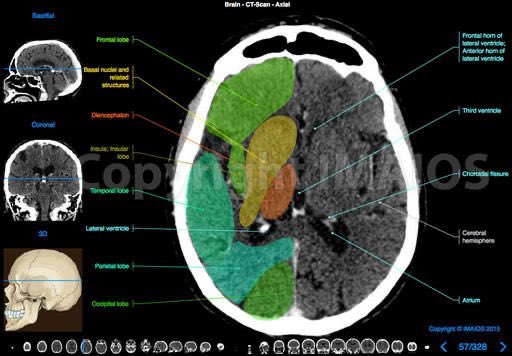

▫️نبدأ بأشعة مقطعية طبيعية للرأس

Normal Head CT scan

▫️صور تشريحية جدا رائعة 🧠🌟